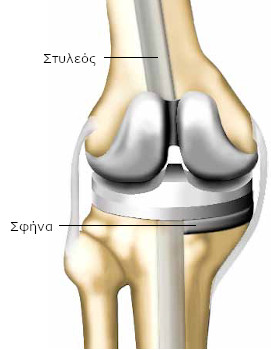

Καθώς το γόνατό σας έχει φθαρεί από αρθρίτιδα, η άρθρωσή σας έχει αντικατασταθεί από πρόθεση (πρόθεση γόνατος). Αποτελείται από ένα τμήμα τοποθετημένο στο μηριαίο και ένα δεύτερο στην κνήμη. Πρόκειται για ολική πρόθεση. Μερικές φορές υπάρχει και ένα τρίτο τεχνητό μέρος στο ύψος της επιγονατίδας (πρόθεση επιγονατίδας).

Τα τεχνητά μέρη της άρθρωσης είναι στερεωμένα στο οστό με ή χωρίς τη χρήση ειδικού τσιμέντου. Τα δύο μέρη της πρόθεσης ολισθαίνουν μεταξύ τους και αναπαράγουν τη φυσιολογική λειτουργία της άρθρωσης.

Ο χειρουργός μπορεί να χρειαστεί να προβεί σε επιπλέον ενέργειες. Ο στυλεός περνά από το κέντρο του μηριαίου και της κνήμης και σταθεροποιεί την πρόθεση. Εφόσον το οστό έχει φθαρεί, είναι πιθανό να χρησιμοποιηθούν σφήνες για να συμπληρωθούν τα κενά.